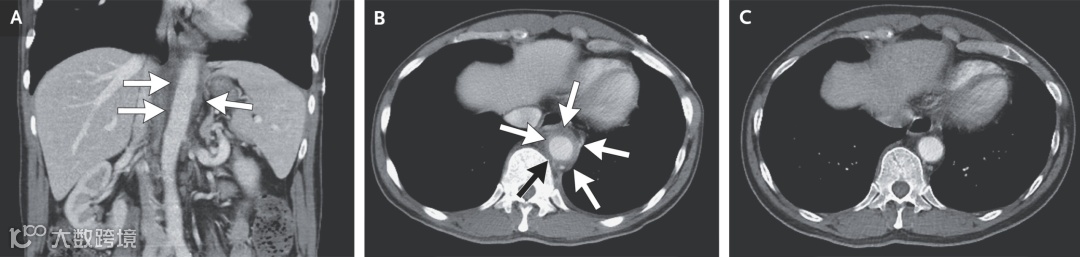

管壁改变:降胸主动脉和腹主动脉的管壁呈现出环形增厚,且明显强化。

周围环境:注意看血管周围,出现了脂肪条索影 (Fat Stranding),这是急性炎症波及周围组织的典型信号。这不是血管硬化,这是血管炎。

影像见证奇迹(图C): 5 个月后复查 CT

那个曾经肿胀、增厚、周围模糊的主动脉壁,变得光滑、纤薄、界限清晰。

周围的脂肪条索影完全消失。如果不看之前的片子,你甚至不敢相信这段血管曾经经历过一场剧烈的“火灾”。